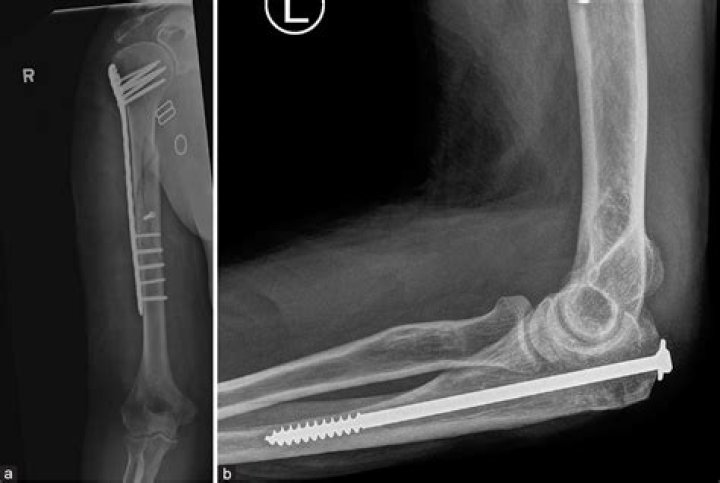

Can you have an MRI with orthopedic hardware?

The authors conclude MRI is safe in patients with orthopedic implants because implant displacement and heating pose little risk to patients. A risk-to-benefit ratio is warranted, however, to assess the clinical utility and necessity of the study.

Most orthopedic implants are made from nonferromagnetic materials and, therefore, tend to be acceptable for patients undergoing MRI examinations.

In general, MRI with field strengths up to 7.0 T can safely be used in patients with orthopedic implants, because the risk of implant-based complications is extremely low. In this review, 3 of the studies cited areas of concern regarding displacement of orthopedic implants during MRI.